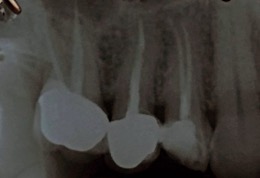

Una corretta terapia canalare con un perfetto sigillo a livello degli apici delle radici è fondamentale. I denti devitalizzati impropriamente possono creare ulteriori problemi che poi andranno a ripercuotersi sulle cure effettuate successivamente come le ricostruzioni e le corone protesiche con conseguente fallimento del piano terapeutico.

Capita spesso di incontrare denti già devitalizzati in maniera impropria che necessitano, seppur asintomatici, di essere ritrattati per evitare che i granulomi infetti visibili radiograficamente si evolvano riassorbendo tutto l’osso sottostante.